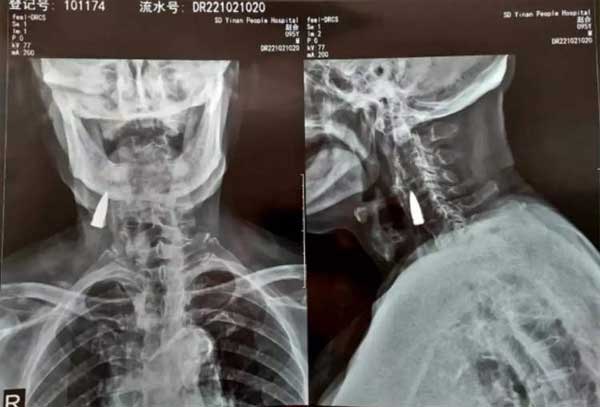

Viên đạn nằm trong cổ 77 năm mà bệnh nhân không hề hay biết. (Ảnh: Oddity Central)

Tuy nhiên, kết quả chụp X-quang không phát hiện bất cứ tổn thương nào ở cổ của cụ Zhao nhưng lại có một vật thể lạ nằm bên trong. Sau đó, vật thể lạ được xác định là một viên đạn, nhưng cụ Zhao cũng không nhớ mình bị đạn găm vào cổ khi nào.

Cụ Zhao cho rằng viên đạn xuất hiện trong cổ là từ năm 1944, khi ông bị trúng đạn trong lần vượt sông. Viên đạn được cho đã xuyên qua mũi trái, xuống hàm trên trước khi chui xuống cổ. Nhưng đây cũng chỉ là suy đoán của cụ Zhao, còn sự thật vẫn là ẩn số.

Sau khi kiểm tra phim chụp X-quang, bác sĩ thông báo với cụ Zhao và gia đình rằng viên đạn nằm sát gần một số mạch máu chính nhưng nó vẫn chưa gây ra bất cứ vấn đề xấu nào cho sức khỏe bệnh nhân, nên tốt nhất là để nó nằm yên tại chỗ. Cụ Zhao cũng đồng tình với phương án của bác sĩ.